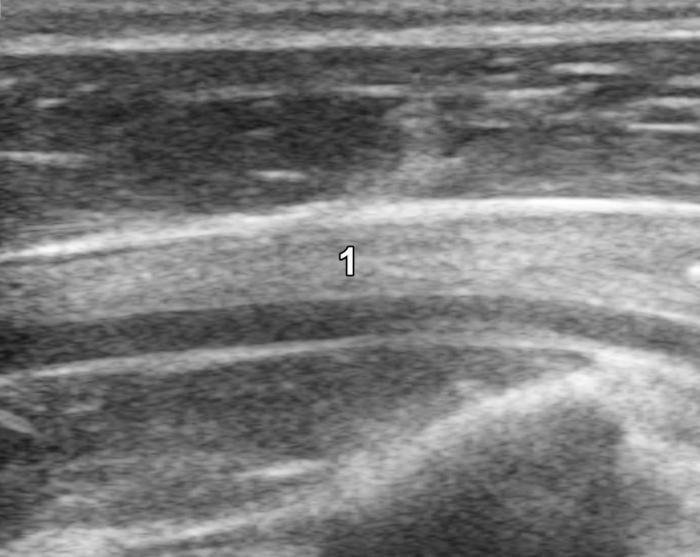

La glándula tiroides en perros y gatos está constituida por dos lóbulos situados a ambos lados de la tráquea cervical, con disposición longitudinal y una forma fusiforme o alargada que se extiende desde el cartílago cricoides hasta la entrada torácica superior2. En condiciones normales, cada lóbulo presenta contornos bien definidos, cápsula hiperecogénica delgada y parénquima homogéneo, con una ecogenicidad generalmente igual o ligeramente superior al músculo esternohioideo adyacente3,8. En la imagen transversal, los lóbulos suelen adoptar una configuración oval o ligeramente triangular (Figura 1); en longitudinal, se observa una forma alargada con extremos redondeados y orientación paralela a los vasos carotídeos y la tráquea1 (Figura 2).

La localización anatómica superficial de la glándula, junto con su estructura relativamente uniforme, facilita su identificación mediante ultrasonografía de alta resolución. Entre los reparos anatómicos más importantes para su localización se encuentran las arterias carótidas comunes (laterales), la tráquea (medial) y los músculos esternotiroideos (ventrales), mientras que el esófago puede constituir una referencia dorsal del lóbulo izquierdo15 (Figuras 3 y 4).